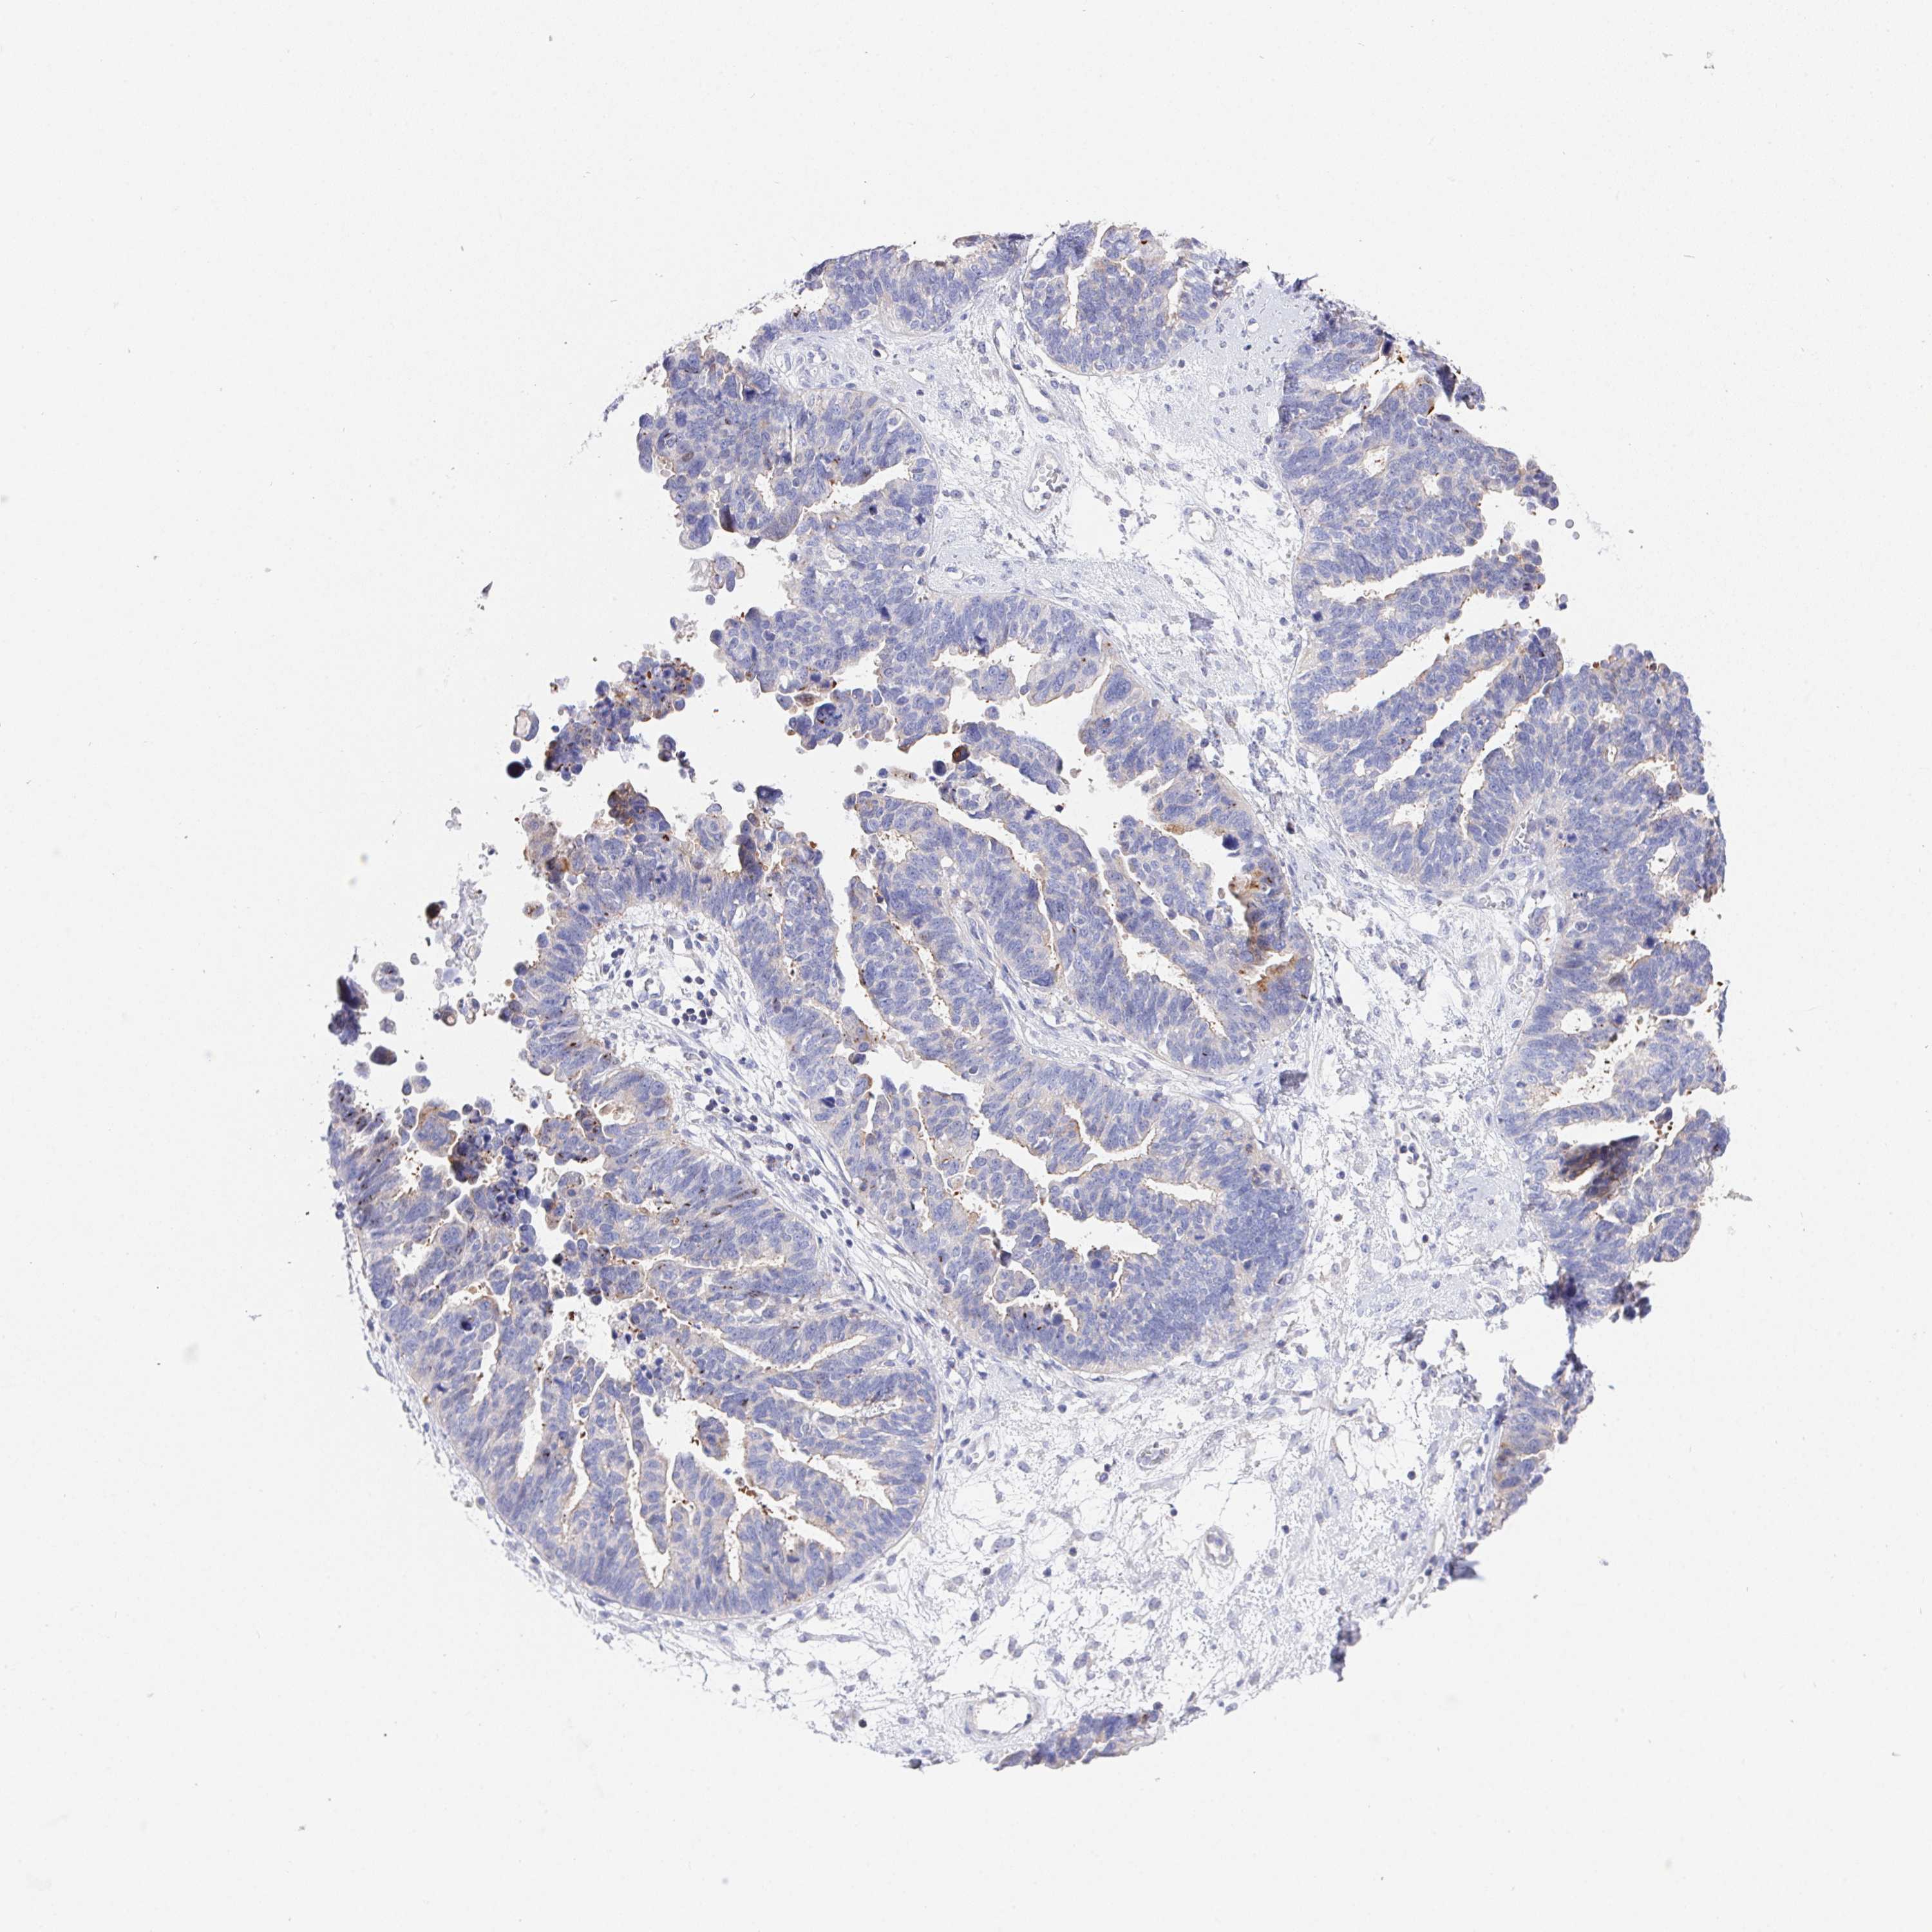

OVARIAN CANCER - Protein expressioni

A mouse-over function shows sample information and annotation data. Click on an image to view it in a full screen mode. Samples can be filtered based on level of antibody staining by selecting one or several of the following categories: high, medium, low and not detected. The assay and annotation is described here.

Note that samples used for immunohistochemistry by the Human Protein Atlas do not correspond to samples in the TCGA dataset.

Antibody stainingi

Antibody staining in the annotated cell types in the current human tissue is reported as not detected, low, medium, or high, based on conventional immunohistochemistry profiling in selected tissues. This score is based on the combination of the staining intensity and fraction of stained cells.

Each image is clickable and will lead to virtual microscopy that enables deeper exploration of all samples and also displays staining intensity scores, fraction scores and subcellular localization as well as patient and tissue information for each sample.

Antibody HPA064183

Staining

High

Medium

Low

Not detected

Intensity

Strong

Moderate

Weak

Negative

Quantity

>75%

75%-25%

<25%

None

Location

Nuclear

Cytoplasmic/membranous

Cytoplasmic/membranous,nuclear

Cystadenocarcinoma, serous, NOS

Cystadenocarcinoma, mucinous, NOS

Carcinoma, endometroid